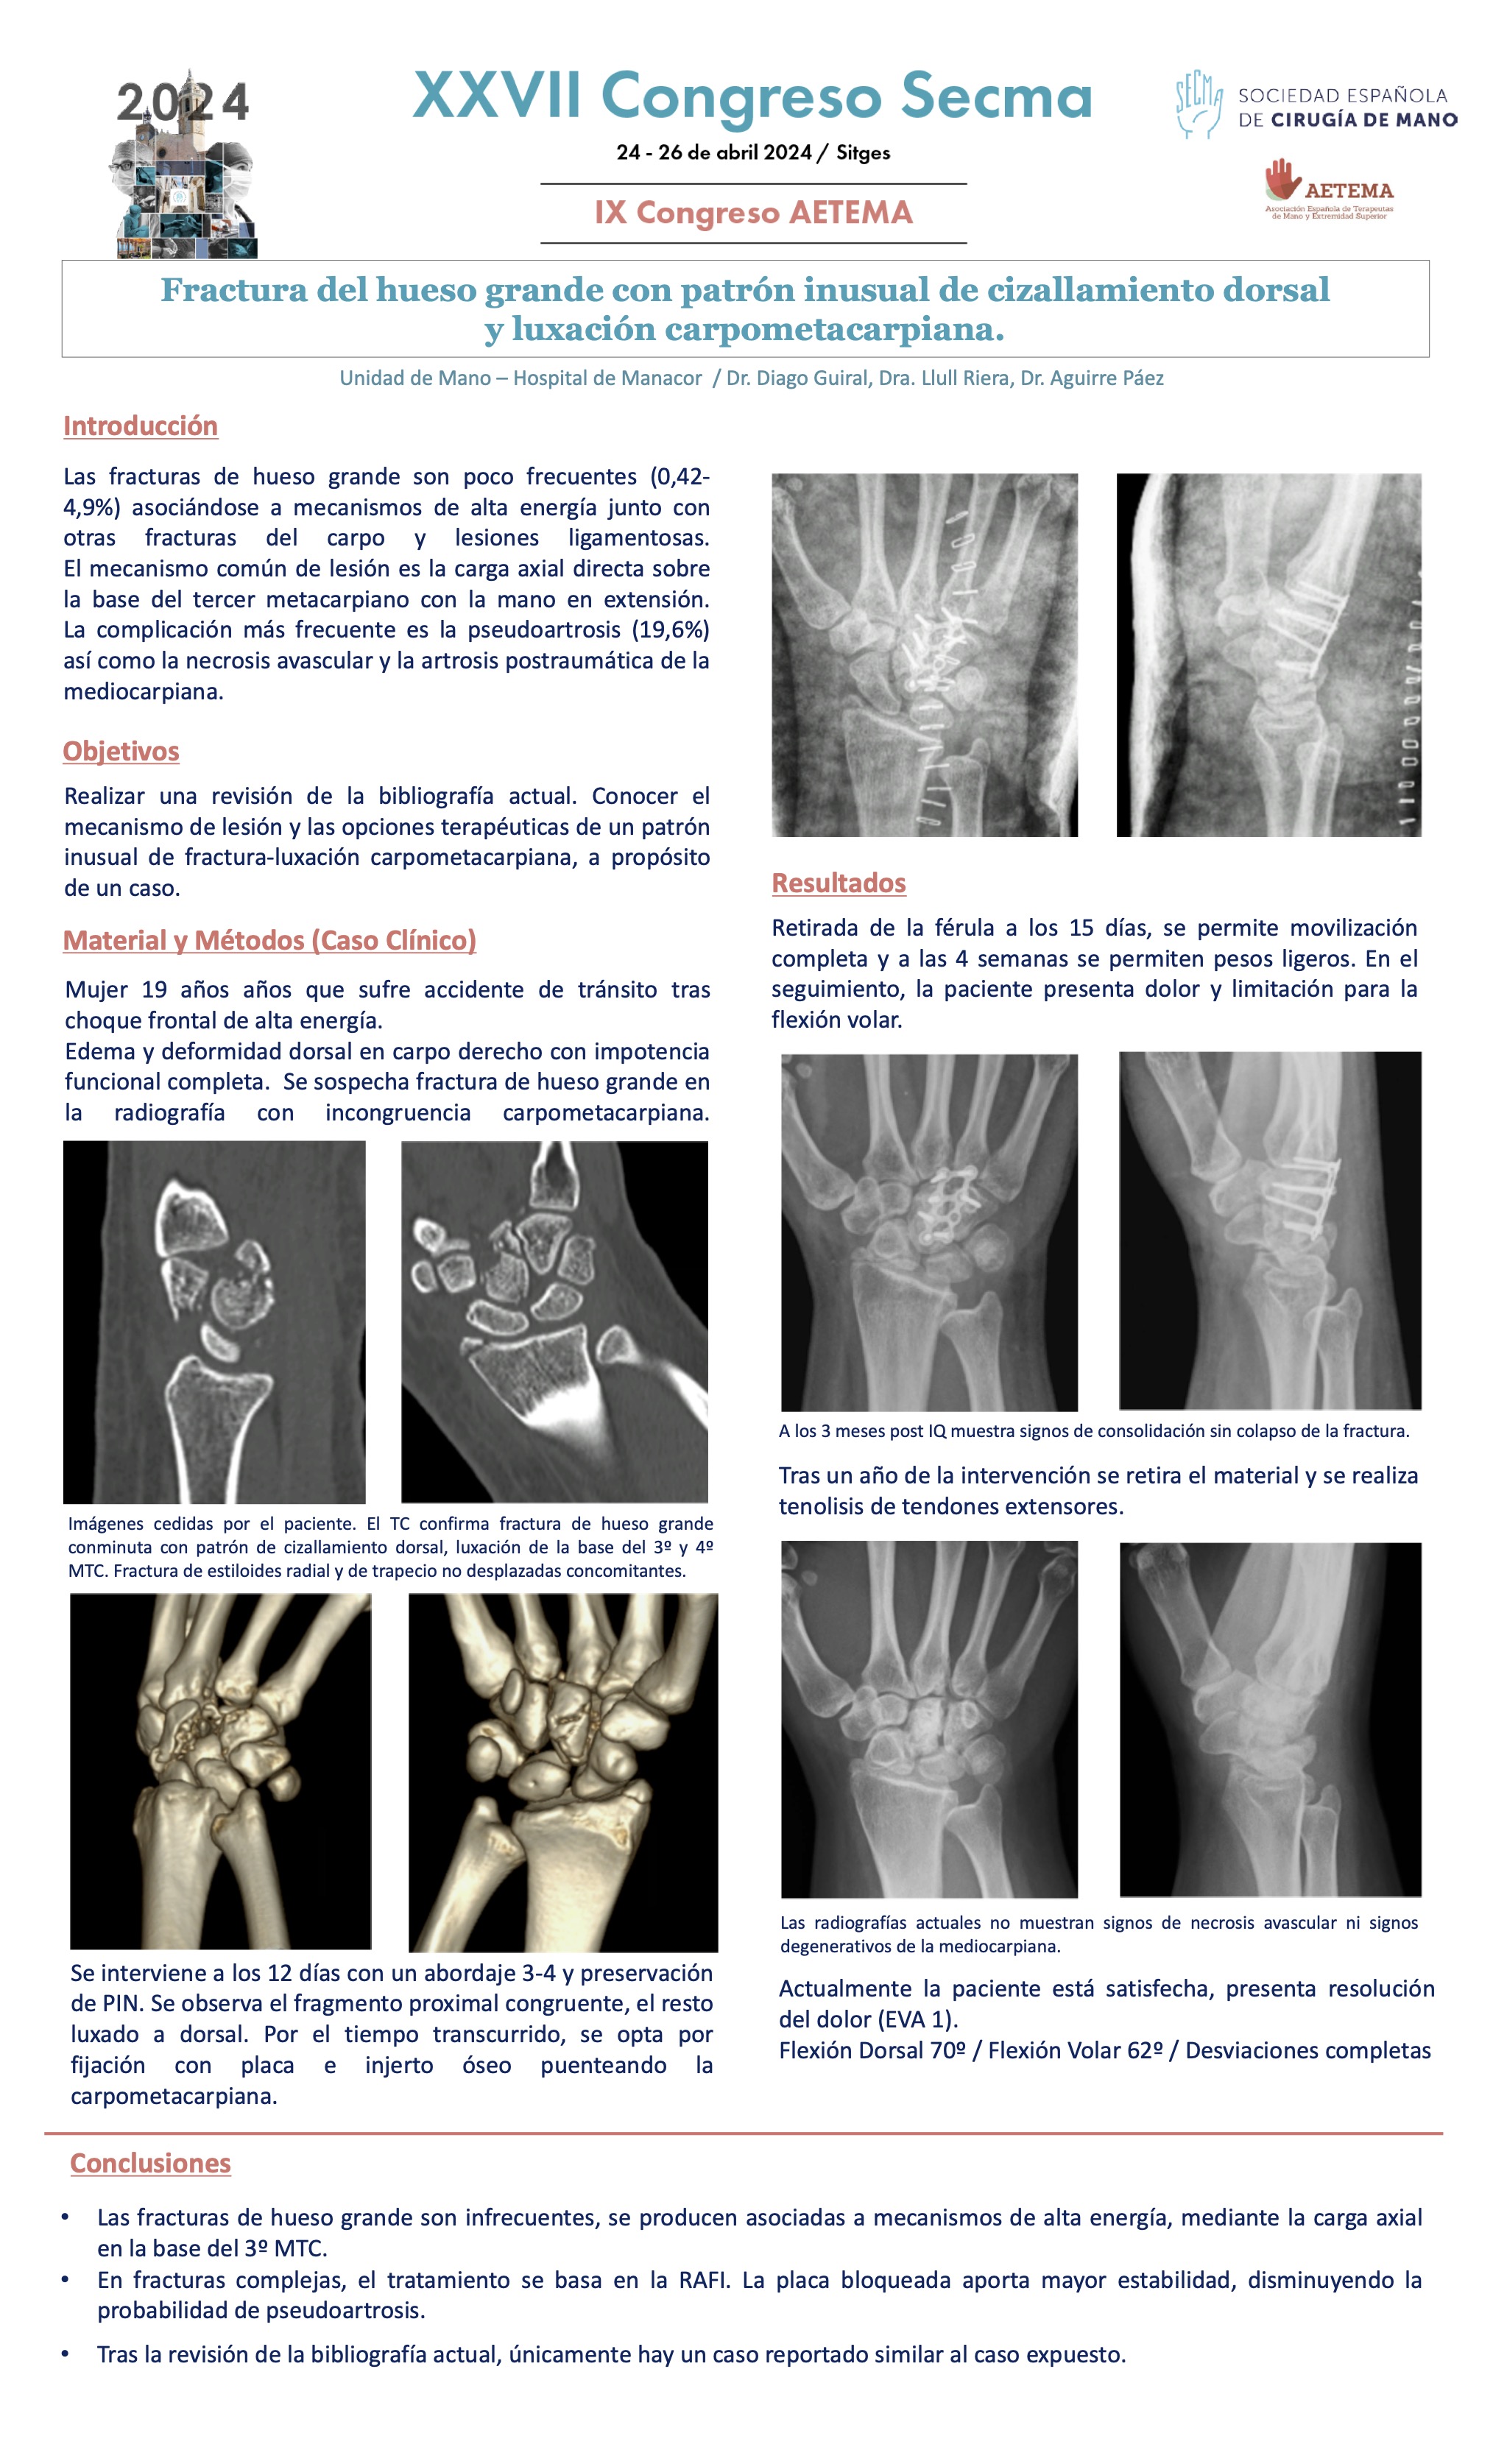

Temática: Comunicaciones sobre Fracturas lesiones articulares e inestabilidades